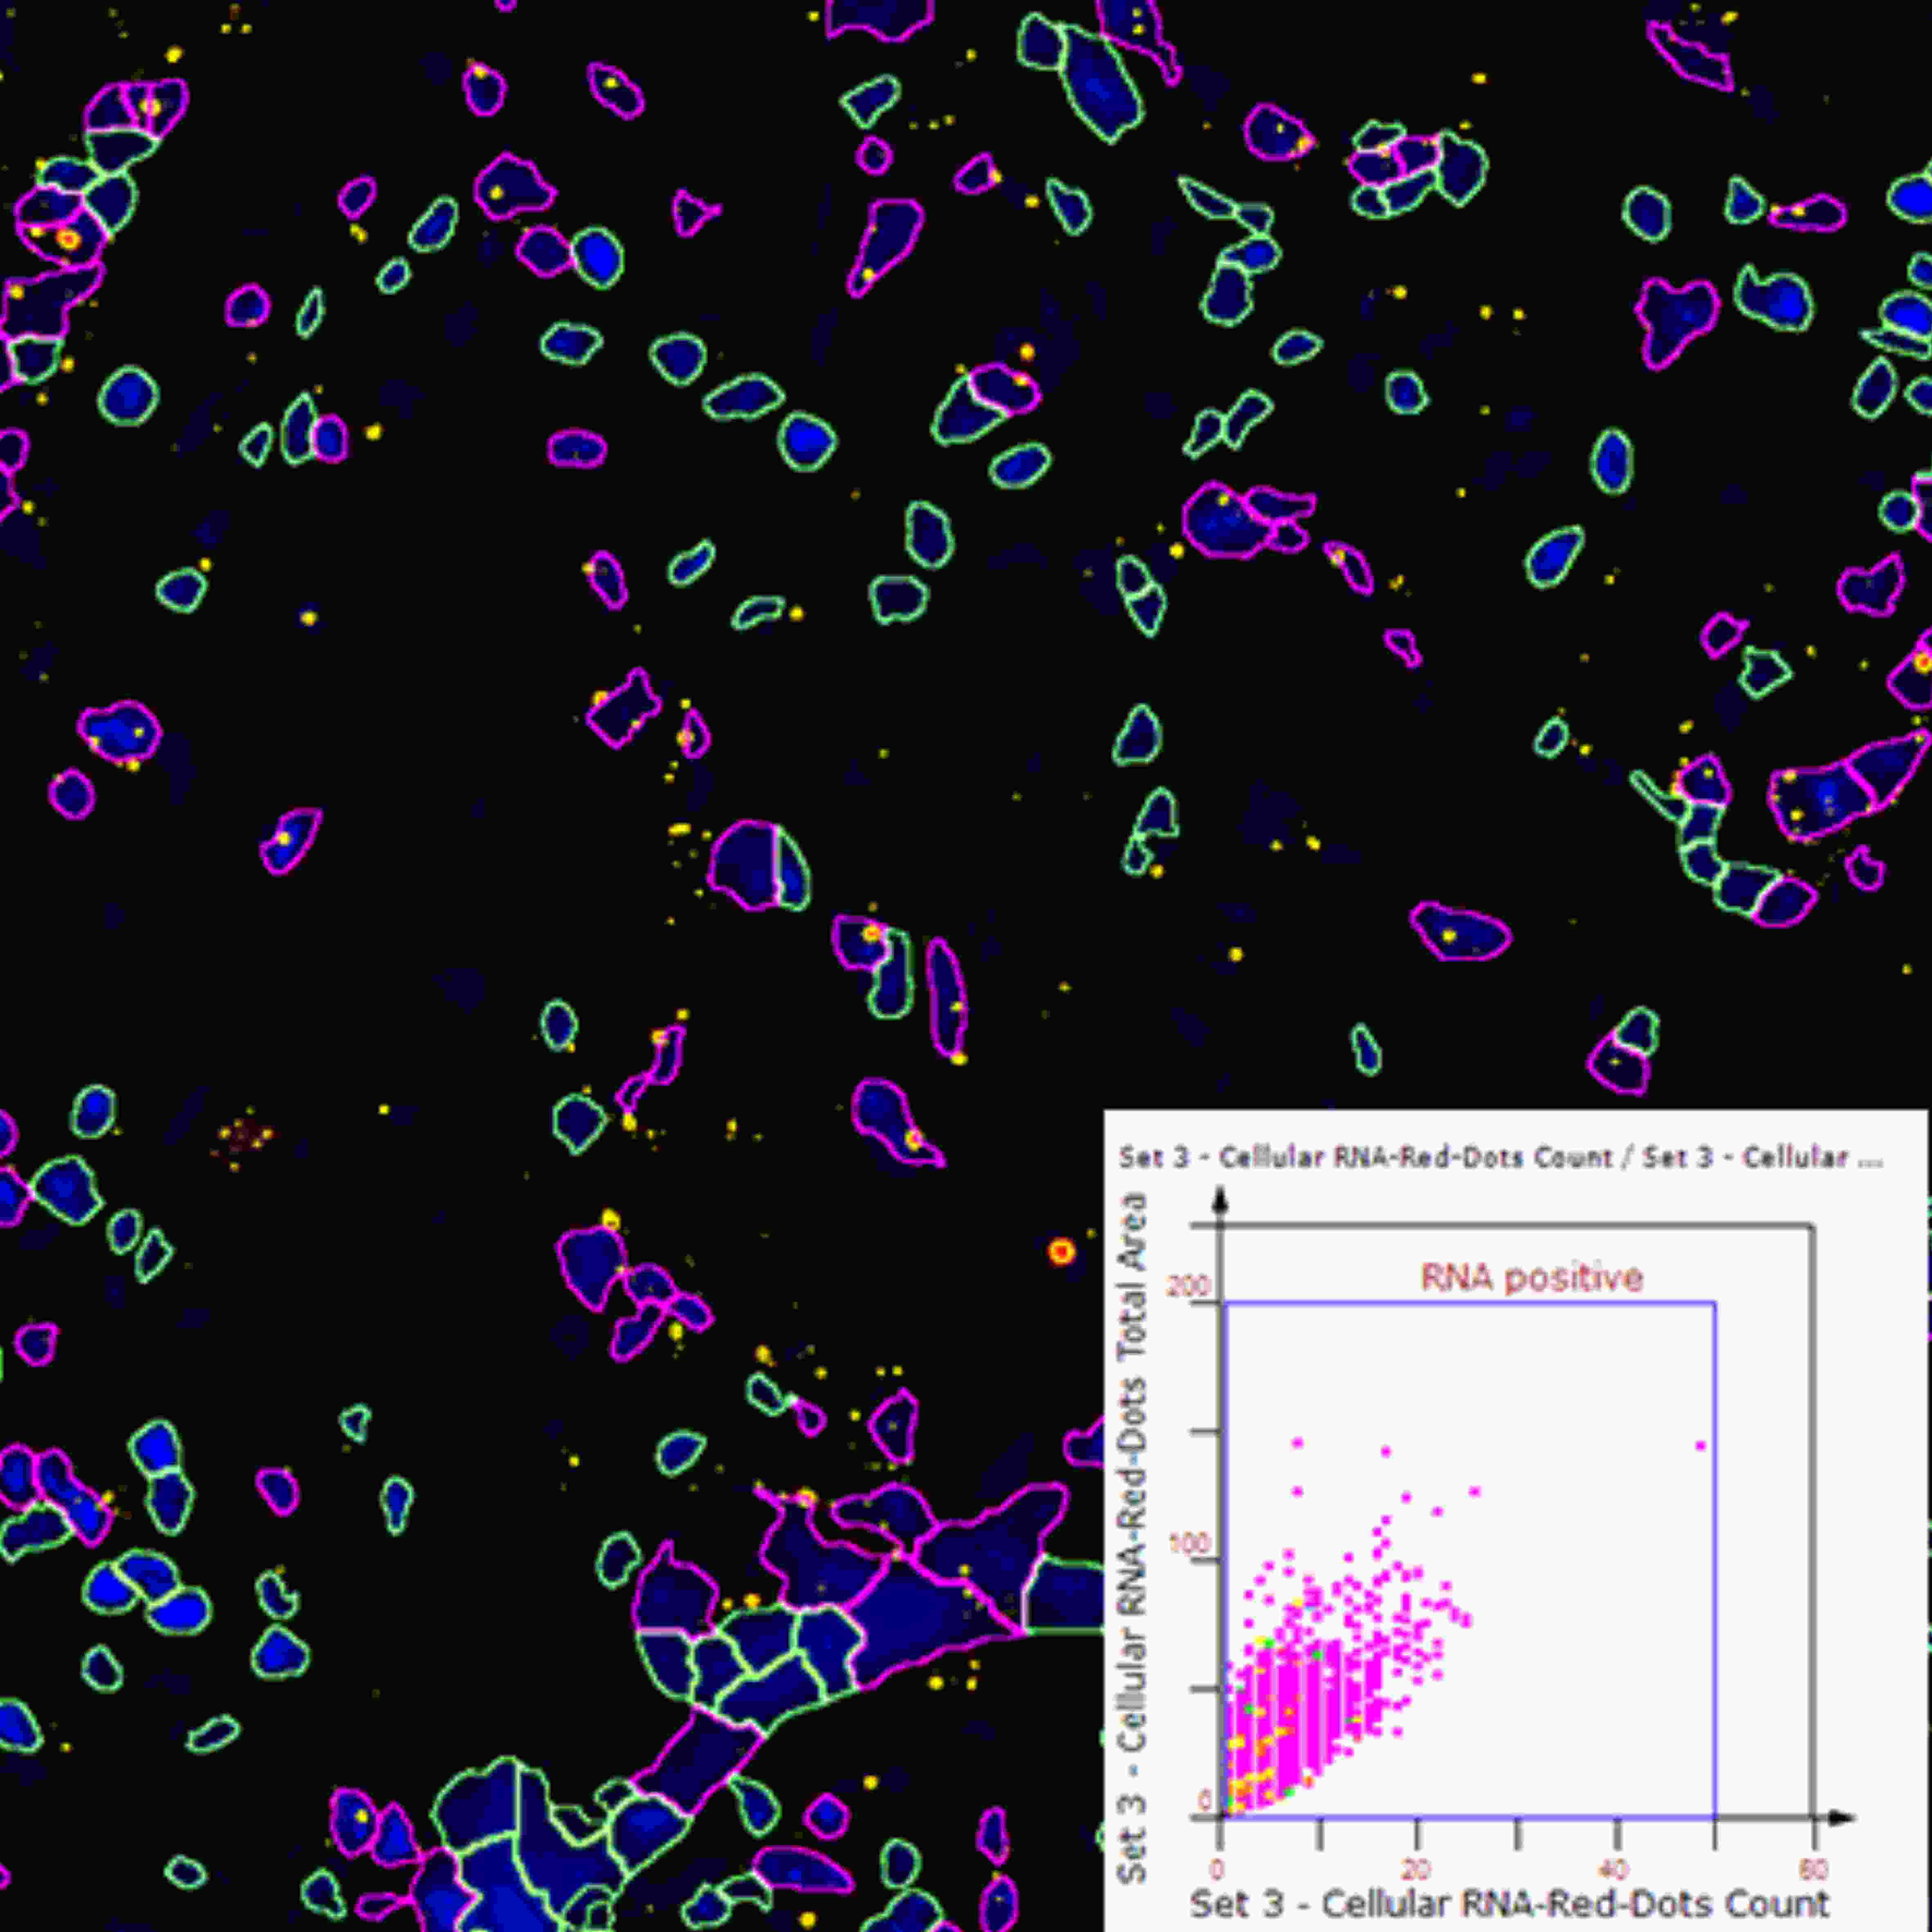

RNA原位杂交可提供RNA在组织细胞的空间表达信息。Dot点状marker分析功能可自动计算细胞核/细胞质内RNA Scope数目。除此之外,该功能也适用于FISH等点状marker分析。

分析内容:总FISH点计数、单个细胞中FISH点的平均个数、FISH点荧光强度、单个细胞面积